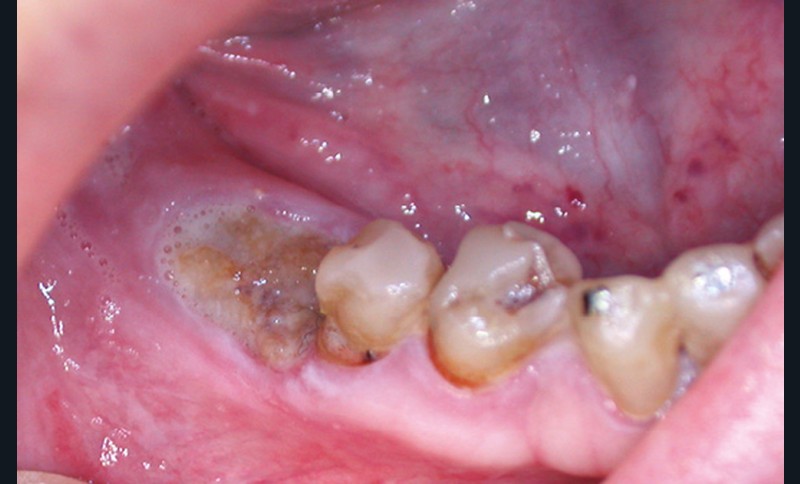

Un contrôle à la fréquence de 4 à 6 mois devra être instauré. La fréquence sera adaptée à l’état bucco-dentaire et à l’appréciation des facteurs locaux de susceptibilité du patient (risque carieux, biotype parodontal). La motivation à l’hygiène et l’efficacité du contrôle de plaque devront être entretenues. Les soins conservateurs précoces seront bien entendu privilégiés. Dans ce contexte, il ne faudra pas hésiter à conserver des dents d’une valeur intrinsèque faible pour éviter le recours à un geste chirurgical. En cas de carie délabrante ou de mobilité modérée, les soins conservateurs devront être privilégiés (endodontie, contentions). En cas d’infection, un traitement conservateur devra également être envisagé (fig. 2).

La priorité devra être donnée à la suppression de la composante infectieuse. Ainsi, pour éviter une extraction, il pourra être légitime de préconiser la conservation d’une dent à l’état de racine sur laquelle le traitement endodontique aura permis la stérilisation du foyer infectieux. Cependant, ce traitement conservateur ne sera retenu qu’à condition de pouvoir conserver durablement cette racine par une obturation étanche à l’aide d’un matériau de reconstitution définitif. Toutefois, pour contrôler l’infection, l’extraction pourra être nécessaire d’emblée ou en cas d’échec d’un traitement conservateur.